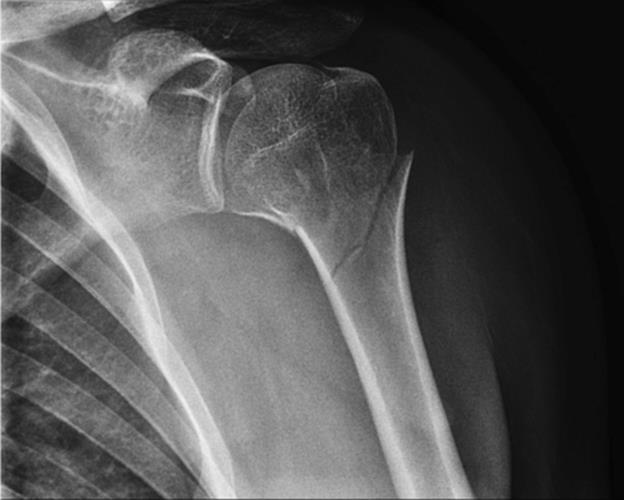

· Early referral to an orthopedic surgeon is advised for Type III–VI injuries (Figure 2.5)

Figure 2.5 Grade III AC separation. Note the elevation of the distal clavicle relative to the acromion suggestive of injuries to both the acromioclavicular and coracoclavicular ligaments. (Reproduced with permission of the Department of Emergency Medicine, Feinberg School of Medicine, Northwestern University.)